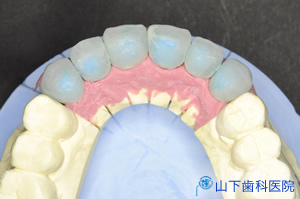

| 精密な型取り、咬み合せ取りを行って、できた作業模型(シリコンガム付き)の上で、歯科技工士が上顎6前歯のレジン製のモックアップ単独冠を作りました。 | ![]() |

| モックの単独冠を試適して、見える歯の部分(歯冠部)の大きさ、長さ、バランス、歯冠部歯軸の見かけの向き、咬み合せ運動時の下の歯との接触状態などを調整します。 全体の口元の審美性を高めるために、犬歯の先端の向きをできるだけ内側に倒し、それより前4本も先端はやや内側に向けます。 上の前歯の裏側は下の前歯が前方に出てくる顎運動をガイドする重要な役割をするため、歯の長さを短くしないで内側に向けるためには、前歯部での上下の隙間が相当に必要で、そのために奥歯で決まる咬み合せの高さを挙げたのです。 |